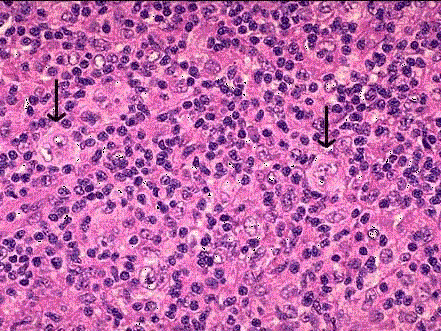

图霍奇金病镜下观,箭头所指为肿瘤细胞。 相应名称是 ( )A.Reed-Sternberg细胞(又称镜影细胞)B.霍奇金细胞(又称H细胞...

问题 图霍奇金病镜下观,箭头所指为肿瘤细胞。 相应名称是 ( )

选项 A.Reed-Sternberg细胞(又称镜影细胞) B.霍奇金细胞(又称H细胞) C.L& H细胞(又称爆米花细胞) D.陷窝细胞(又称L细胞) E.多核性R-S细胞(又称巨大R-S细胞)

答案 A